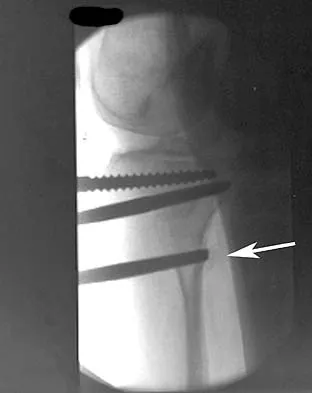

A 26-year-old woman sustained a nondisplaced femoral neck fracture and treatment consisted of use of percutaneous cannulated screws. At her 3-month follow-up visit, she reports hip pain and is unable to ambulate. A radiograph is shown in Figure 1. What is the next most appropriate treatment?

Explanation

Femoral neck fracture nonunion is a challenging problem for orthopaedic surgeons. Vertical fractures are more prone to nonunion due to shear stress rather than compressive forces across the fracture site. Several authors have suggested these fractures are more common in young adults due to injury type and bone composition. It is widely regarded that an effort should be made to salvage the femoral head if vascularity remains. The most common method to treat this complication is valgus intertrochanteric osteotomy of the femur. This functionally makes a vertical fracture more horizontal, converting shear into compressive forces. It also helps correct the varus position of the fracture nonunion. Hartford JM, Patel A, Powell J: Intertrochanteric osteotomy using a dynamic hip screw for femoral neck nonunion. J Orthop Trauma 2005;19:329-333.